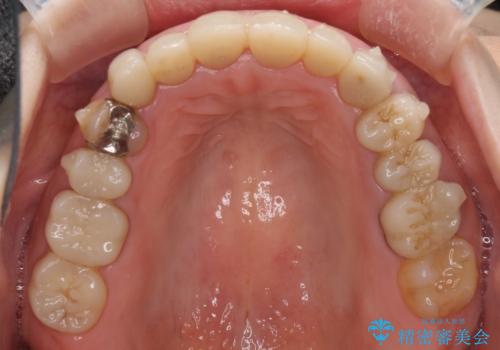

- 下顎の前歯に激痛を覚えて来院された患者様です。

取り急ぎ下顎前歯数歯の根管治療を、銀座しらゆり歯科医院長の林先生にお願いし、それ以外に気になっている、不自然な色調のクラウン、金属部分が見えてブラッシングがしにくいインプラント補綴、口元の突出感、出血のしやすい歯周ポケットなど、全てを解決するための治療を行うこととしました。